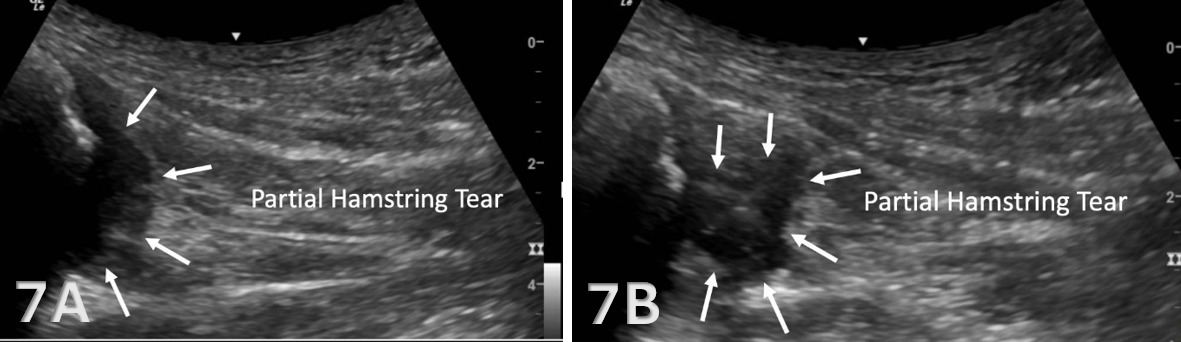

The proximal medial hamstrings consist of both the semitendinosus and semimembranosus, and the proximal lateral muscle, the biceps femoris, all of which originate on the ischial tuberosity.8 The biceps femoris long head and the semitendinosus muscle originate from a conjoint tendon at the medial posterior aspect of the ischial tuberosity, while the semimembranosus attaches more laterally and anteriorly.9,10

The starting point for examining the proximal hamstring tendon and muscle is at the osseous landmark – the ischial tuberosity.12,13,17–19 The ischial tuberosity can almost always be palpated, giving the examiner a perfect location to begin their scan. The proximal hamstring can be scanned in both the long axis (LAX) and the short axis (SAX). In the LAX view, depending on the probe width and size, one should start proximally to visualize the hyperechoic reflection of the bony cortex of the ischial tuberosity, with its large acoustic shadow underneath. In LAX, the proximal hamstring tendon fibers of the long head of the biceps femoris and the semitendinosus conjoint tendon should be easily seen coming off the attachment of the ischial tuberosity with a clear hyperechoic fibrillar structure running distally from the insertion site on the anterior lateral origin of the ischial tuberosity. The semitendinosus fibers can be easily seen as they reach the ischial tuberosity directly. Lateral to the hamstring muscle complex, the sonographer will see the sciatic nerve that appears as a fascicular, flattened structure that descends between and deep to the long head of the biceps femoris and semimembranosus tendon.1 The probe can be turned 90 degrees for viewing in the SAX. If the probe is moved slightly distally in the SAX view, the biceps femoris will appear as a triangular shape. As the examiner moves distally along the biceps muscle belly, the size will decrease until it appears to disappear. In both views, some toggling may be required to reduce anisotropy.